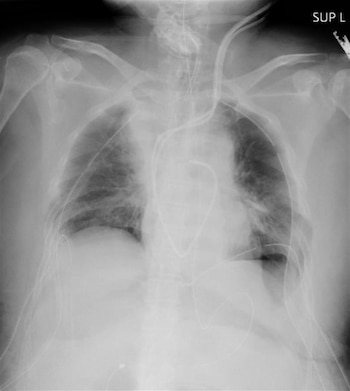

La paciente es una mujer afectada de neumonía tras contagiarse de coronavirus a finales del año pasado, y a la que se aplicó respiración asistida después de que sus pulmones resultaran dañados por el virus, según informó el citado centro en un comunicado.

Un equipo médico compuesto por unos 30 especialistas le realizó la operación de trasplante en la víspera, y ha evolucionado favorablemente desde entonces.

Se espera que la paciente, que ya ha dado negativo por COVID-19 y ha permanecido tres meses con respiración asistida, sea dada de alta dentro de dos meses y pueda hacer vida normal en un mes más.

Los donantes fueron el marido y el hijo de la paciente, que donaron respectivamente parte de sus pulmones izquierdo y derecho.

Según el Hospital Universitario de Kioto, se trata de la primera operación de este tipo en el mundo realizada con éxito a partir de donantes vivos.

Anteriormente se habían realizado en otros países varias decenas de operaciones de trasplante pulmonar a partir de donantes con muerte cerebral, pero ninguna de estas características, precisó en su nota el hospital nipón.